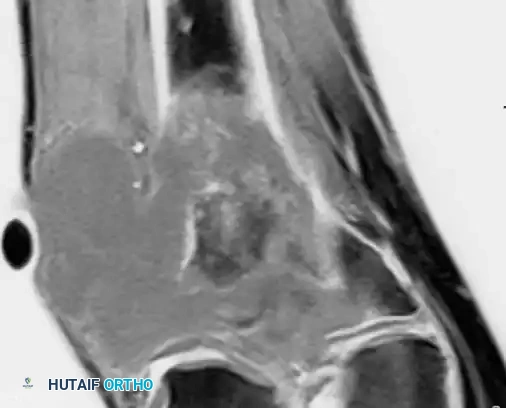

MRI demonstrating extensive bone destruction and a large soft-tissue mass adjacent to a bone infarct.

Magnetic Resonance Imaging (MRI) is the gold standard for local staging. It precisely delineates the intraosseous extent of the tumor, "skip" metastases within the same bone, and the degree of extraosseous soft-tissue extension.